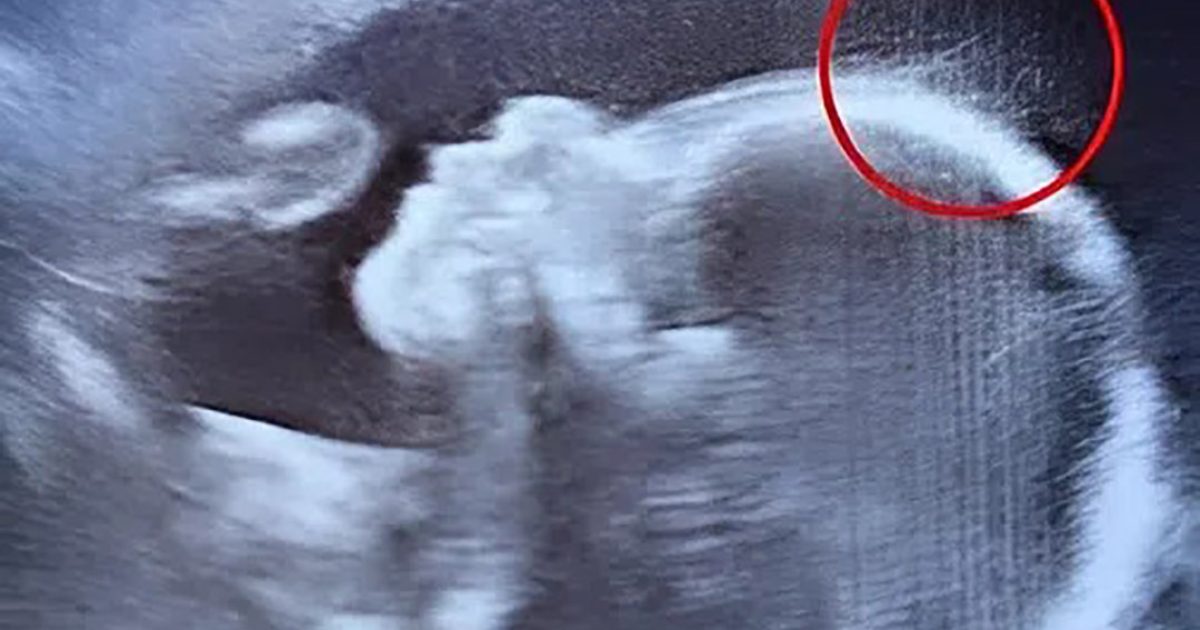

10 septembre 2025 Lors de l’échographie, les médecins ont été stupéfaits. À sa naissance, cette petite fille a bouleversé le monde par sa résilience et sa grâce